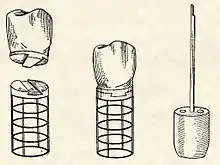

The early part of the 20th century saw a number of implants made of a variety of materials. One of the earliest successful implants was the Greenfield implant system of 1913 (also known as the Greenfield crib or basket).[77] Greenfield's implant, an iridioplatinum implant attached to a gold crown, showed evidence of osseointegration and lasted for a number of years.[77] The first use of titanium as an implantable material was by Bothe, Beaton and Davenport in 1940, who observed how close the bone grew to titanium screws, and the difficulty they had in extracting them.[78] Bothe et al. were the first researchers to describe what would later be called osseointegration (a name that would be marketed later on by Per-Ingvar Brånemark). In 1951, Gottlieb Leventhal implanted titanium rods in rabbits.[79] Leventhal's positive results led him to believe that titanium represented the ideal metal for surgery.[79]